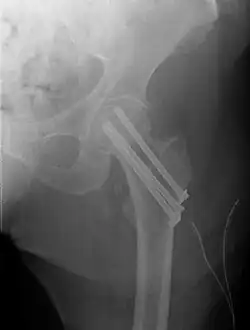

For low-grade fractures (Garden types 1 and 2), standard treatment is fixation of the fracture in situ with screws or a sliding screw/plate device. This treatment can also be offered for displaced fractures after the fracture has been reduced.

Fractures managed by closed reduction can possibly be treated by percutaneously inserted screws.[38]

Closed reduction may not be satisfactory and open reduction then becomes necessary.[43] The use of open reduction has been reported as 8-13% among pertrochanteric fractures, and 52% among intertrochanteric fractures.[44] Both intertrochanteric and pertrochanteric fractures may be treated by a dynamic hip screw and plate, or an intramedullary rod.[43]